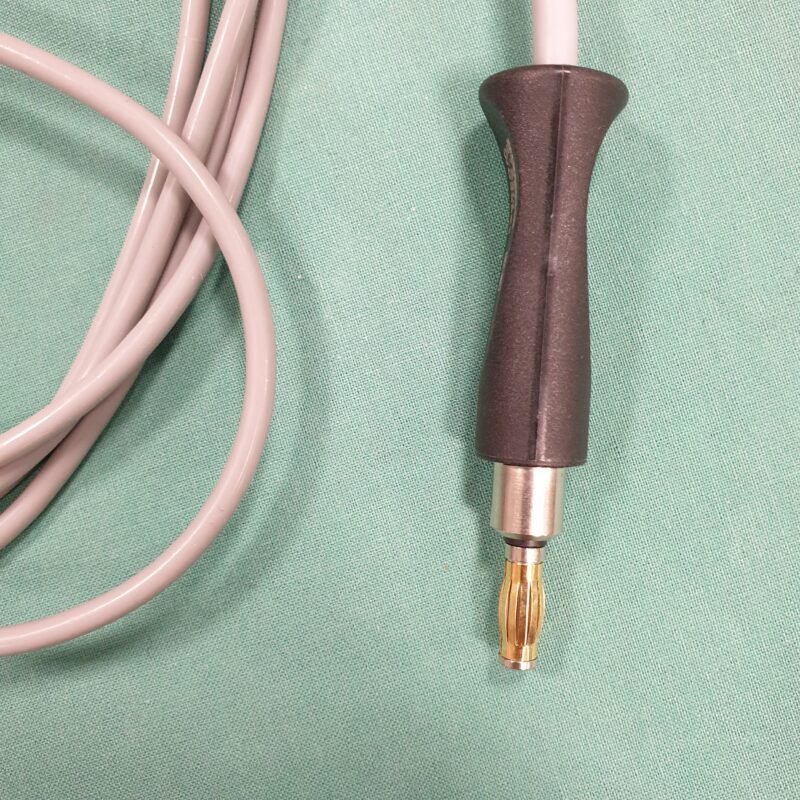

Zustand: Ungeprüft

• Dieses HF Kabel wurde nicht vollständig getestet und könnte daher Funktionsfehler aufweisen.

• Die Bilder sind Teil der Beschreibung – Sie erhalten genau das, was abgebildet ist.

• Der angegebene Preis bezieht sich auf einen einzelnen Fußschalter.

Hinweis: Aufgrund gesetzlicher Bestimmungen werden alle Geräte als defekt für Bastler oder Ersatzteilspender verkauft, auch wenn sie funktionsfähig sind. Der Käufer wird ausdrücklich darauf hingewiesen, dass er bei der Inbetriebnahme die Vorschriften des Medizinprodukte-Durchführungsgesetzes (MPDG) sowie der Medizinprodukte-Betreiberverordnung (MPBetreibV) einzuhalten hat. Eine sicherheitstechnische Kontrolle des Geräts muss wie vorgeschrieben durchgeführt werden. Für die Einhaltung ist der Käufer selbst verantwortlich.